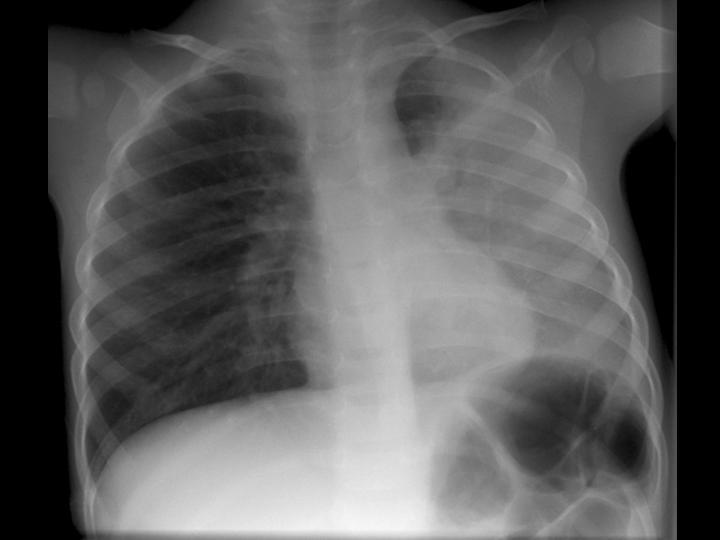

Normal Chest X-ray - A Photo On Flickriver

normal chest x-ray - a photo on Flickriver www.flickriver.com

normal chest ray

Interpretasi Rontgen Toraks - Alomedika

Interpretasi Rontgen Toraks - Alomedika www.alomedika.com